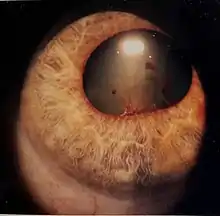

Uveitis (/ˌjuːvi.aɪtɪs/) is inflammation of the uvea, the pigmented layer of the eye between the inner retina and the outer fibrous layer composed of the sclera and cornea.[1] The uvea consists of the middle layer of pigmented vascular structures of the eye and includes the iris, ciliary body, and choroid. Uveitis is described anatomically, by the part of the eye affected, as anterior, intermediate or posterior, or panuveitic if all parts are involved. Anterior uveitis (iridocyclitis) is the most common, with the incidence of uveitis overall affecting approximately 1:4500, most commonly those between the ages of 20-60. Symptoms include eye pain, eye redness, floaters and blurred vision, and ophthalmic examination may show dilated ciliary blood vessels and the presence of cells in the anterior chamber. Uveitis may arise spontaneously, have a genetic component, or be associated with an autoimmune disease or infection. While the eye is a relatively protected environment, its immune mechanisms may be overcome resulting in inflammation and tissue destruction associated with T-cell activation.

- Signs of anterior uveitis include dilated ciliary vessels, presence of cells and flare in the anterior chamber, and keratic precipitates ("KP") on the posterior surface of the cornea. In severe inflammation there may be evidence of a hypopyon. Old episodes of uveitis are identified by pigment deposits on lens, KPs, and festooned pupil on dilation of pupil.

Uveitis is assessed as part of a dilated eye exam.[1] Diagnosis includes dilated fundus examination to rule out posterior uveitis, which presents with white spots across the retina along with retinitis and vasculitis.[1]

The prognosis is generally good for those who receive prompt diagnosis and treatment, but serious complication including cataracts, uveitic glaucoma, band keratopathy, macular edema and permanent vision loss may result if left untreated. The type of uveitis, as well as its severity, duration, and responsiveness to treatment or any associated illnesses, all factor into the outlook.[1]